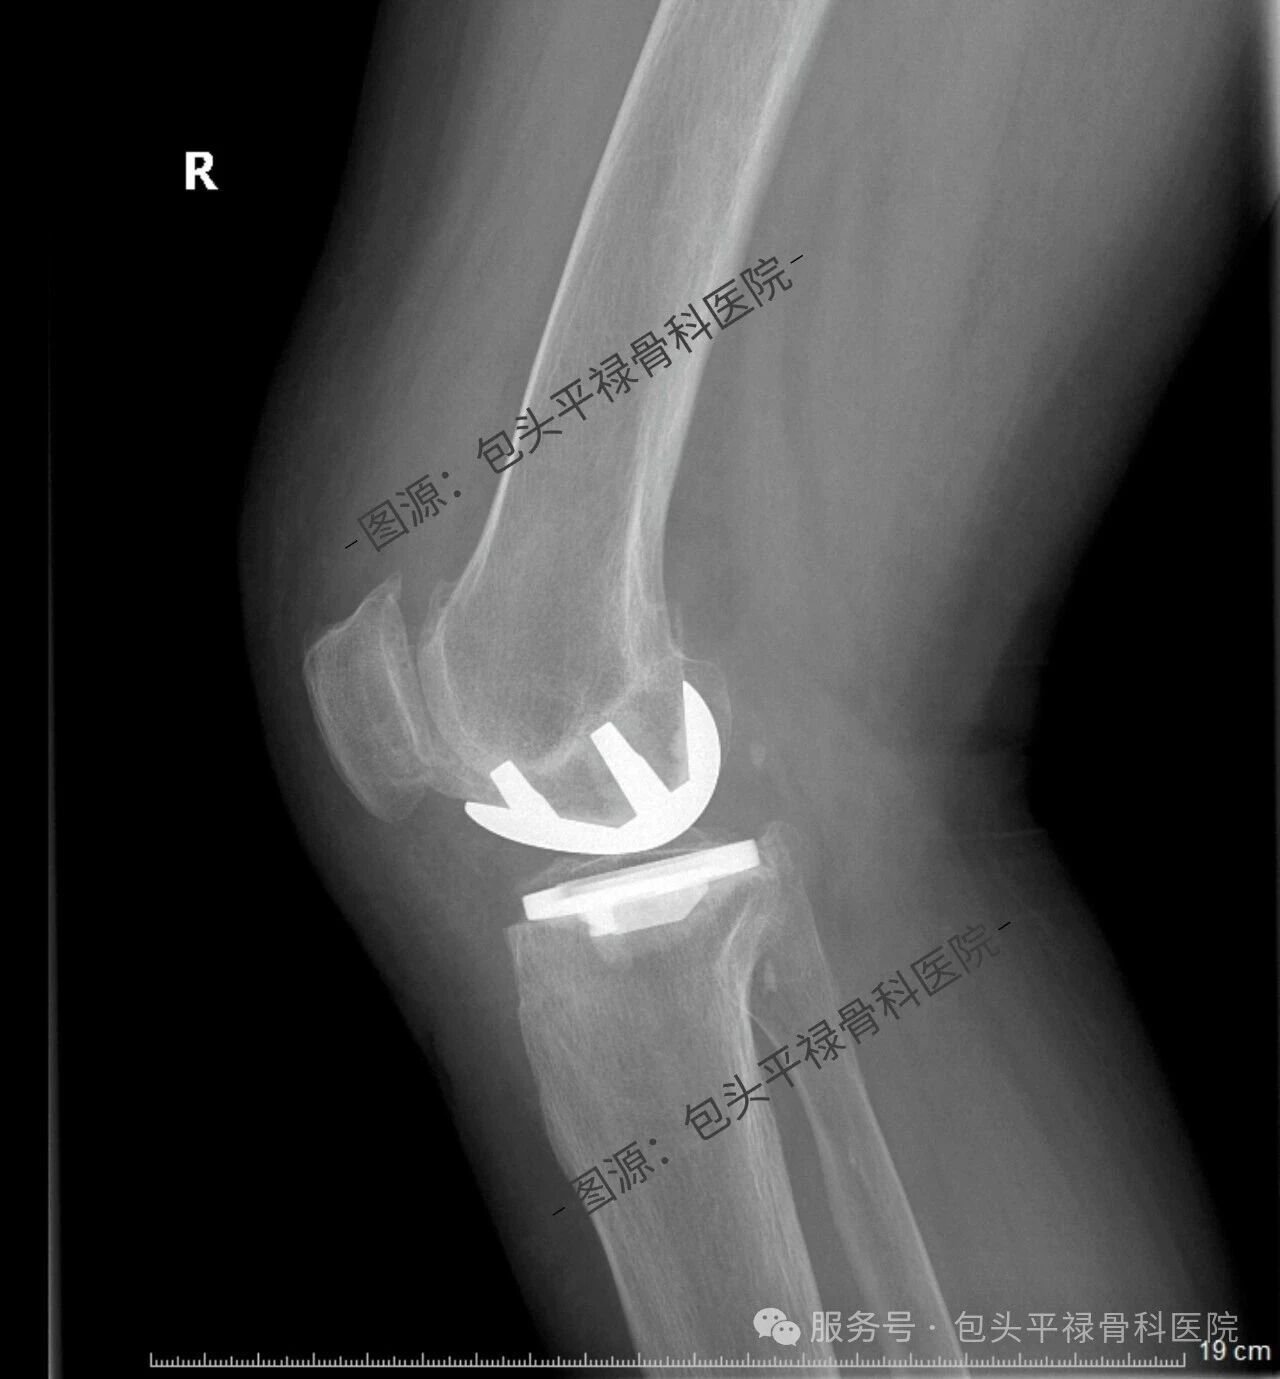

其实,现代医疗技术日趋精准,如果患者的关节炎只局限于膝关节的一个部分(单侧间室),那么TA很可能适合一种更为精准、创伤更小的手术——膝关节单髁置换术。

膝关节单髁置换术相当于“局部翻新”,就是只置换“坏掉房间”的磨损表面,仅将受损的软骨和部分骨质去除,替换为人工假体,而完好的软骨、交叉韧带及其他结构都得以最大程度的保留。

单髁假体的使用寿命并不是一个固定的数值,而是受假体材料、手术技术、患者年龄、体重、活动水平以及术后康复管理等多因素共同影响的。

得益于现代材料科学和外科技术的进步,当代的单髁假体被设计的十分精密和耐用。根据全球范围内大量的临床随访研究数据显示,绝大多数单髁假体都能够为患者提供长期、稳定的服务。